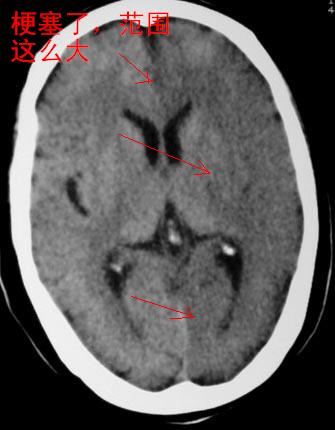

失语及右侧肢体无力3小时

面积这么大,在我们血栓专科也不多见

面积这么大,确实少见

左侧侧裂池消失,脑沟变浅.典型的一侧大脑半球缺血改变.可以诊断:左侧大面积脑梗塞.

左侧大脑半球密度普遍降低,脑沟池消失,考虑大面积梗塞

左侧大脑半球大片密度减低影,脑沟变浅,外侧裂变窄,中线结构无明显移位。左侧大面积脑梗塞,大脑中动脉堵塞所致,愈后不好呀!应早期溶栓啊。

脑梗塞面积这么大,确实少见

是梗塞,不看2楼老师的图,还真不敢随便下结论。

左侧颞顶叶皮层与白质呈大片状低密度影,左侧脑室颞角,及侧裂池受压变小.中线居中.

意见:左侧颞顶叶大面积梗塞(脑膜中动脉梗塞),

典型的左侧大脑半球缺血性脑梗塞早期表现[左侧大脑半球皮质密度减低与脑白质密度一致(脑皮质征),左侧豆状核轮廓模糊,密度与脑白质一致(豆状核征),结合临床有失语及右侧肢体无力3小时]。